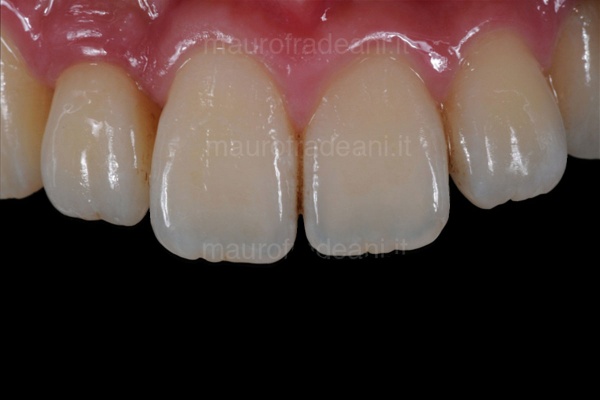

2/5: The front teeth before treatment involving ceramic veneers.

3/5: The 4 ceramic restorations, with a thickness of only a few tenths of a millimeter, are ready to be cemented.

4/5: Final picture of the 4 restorations, showing an excellent integration with the surrounding gingival tissues. The esthetic appearance is significantly improved thanks to the new contours, the new proportions and the dominance of the central incisors.

5/5: After 8 years, the restorations show an excellent functional, biological and esthetic integration.